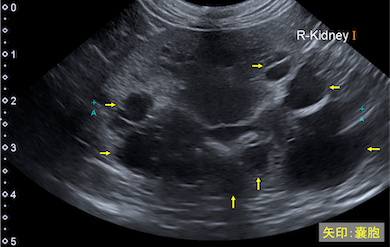

多発性嚢胞腎は猫の遺伝性疾患で、両側の腎臓に嚢胞がたくさんできてしまう病気です。

嚢胞は徐々に大きくなり、正常な腎臓の組織を圧迫するため腎臓の機能が低下してしまいます。

<正常な腎臓の超音波画像>

<多発性嚢胞腎の超音波画像>